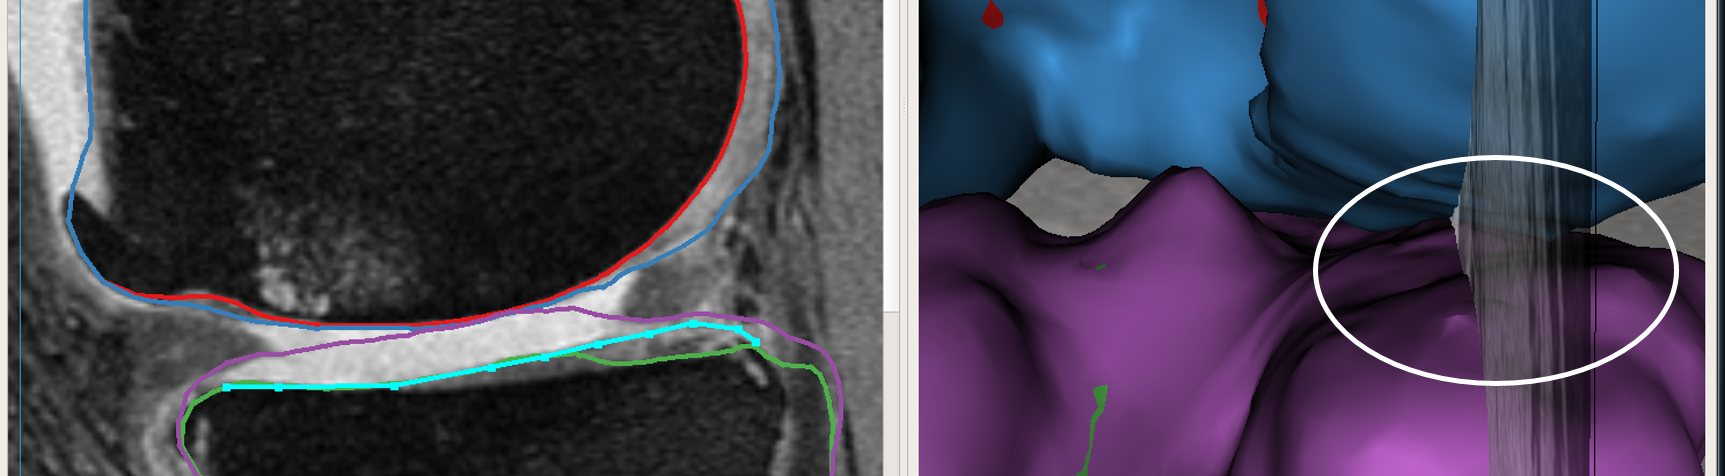

User provided nudge points: The user identified correction is provided as a set of nudge points which guide the segmentation to the correct position. Fig. 3a shows the GUI magnified with the volume and the automated LOGISMOS segmentation results overlayed. The particular slice indicated is a case with severe OA having bright fluid regions improperly segmented as cartilage. The blue line with points are the nudge points indicated by the user approximately identifying the correct cartilage region.

Max-flow re-computation: Following the local graph cost modification the max-flow is recomputed in 3D within a few milliseconds and the updated surfaces rendered onto the GUI. As seen in Fig. 3b the correction made by the nudge points are reflected in the updated cartilage surface overlayed on the image volume.

The above work-flow is repeated to correct the tibial cartilage errors as well. In the intermediate steps following the correction of the femur, the tibia bone and cartilage surfaces appear to worsen. This can be attributed to a combination of the existing graph costs and the graph constraints. Since the tibia cartilage surface has no clear defined edge cost in that region, the surface result moved along with the femur corrected cartilage surface. Subsequently due to the inter-surface distance constraints between the tibial surfaces the tibial bone surface also changed. However once the nudge points provided the appropriate locations for cost modification the erroneous surfaces were corrected (Figs. 3c,d). Note that the corrections made on a single 2D slice resulted in the entire locally affected 3D neighborhood being corrected. This can be appreciated in the corresponding circled regions of the surface model.